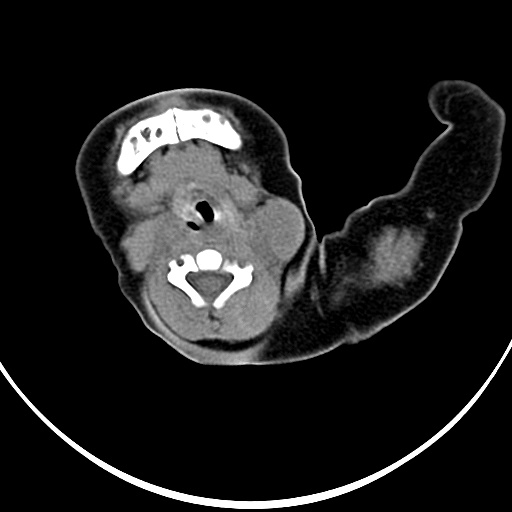

病灶与左侧胸锁乳突肌分界不清,软组织密度,不似囊性改变,从病人的年龄及病变性状首先要除外先天性斜颈(肌性斜颈)可能。

左侧胸锁乳突肌肿大,考虑产伤所致